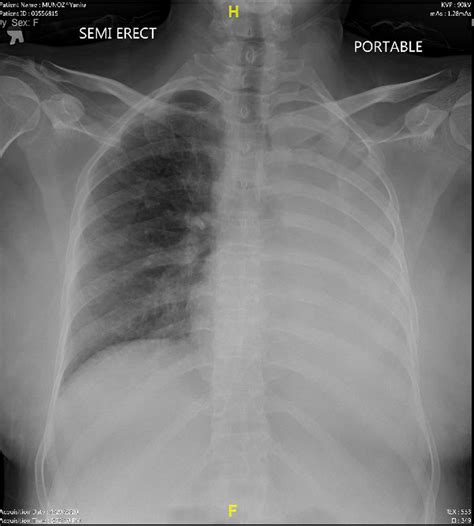

When to Consult a Medical Professional

While most instances of mucus in chest are manageable at home, there are times when professional medical intervention is necessary. You should contact your doctor if the congestion persists for more than a week or if you experience “red flag” symptoms that suggest a more serious bacterial infection or respiratory complication.

Seek medical attention if you notice:

• Difficulty breathing or shortness of breath.

• A fever higher than 101°F (38.3°C) that lasts for more than a few days.

• Chest pain that worsens when coughing or breathing deeply.

• Mucus that is bright red, pink, or dark brown (indicating blood).

• Wheezing that does not go away with home remedies.

💡 Note: If you have a history of asthma or COPD, follow your prescribed action plan immediately when chest congestion begins to ensure it does not escalate into an emergency.